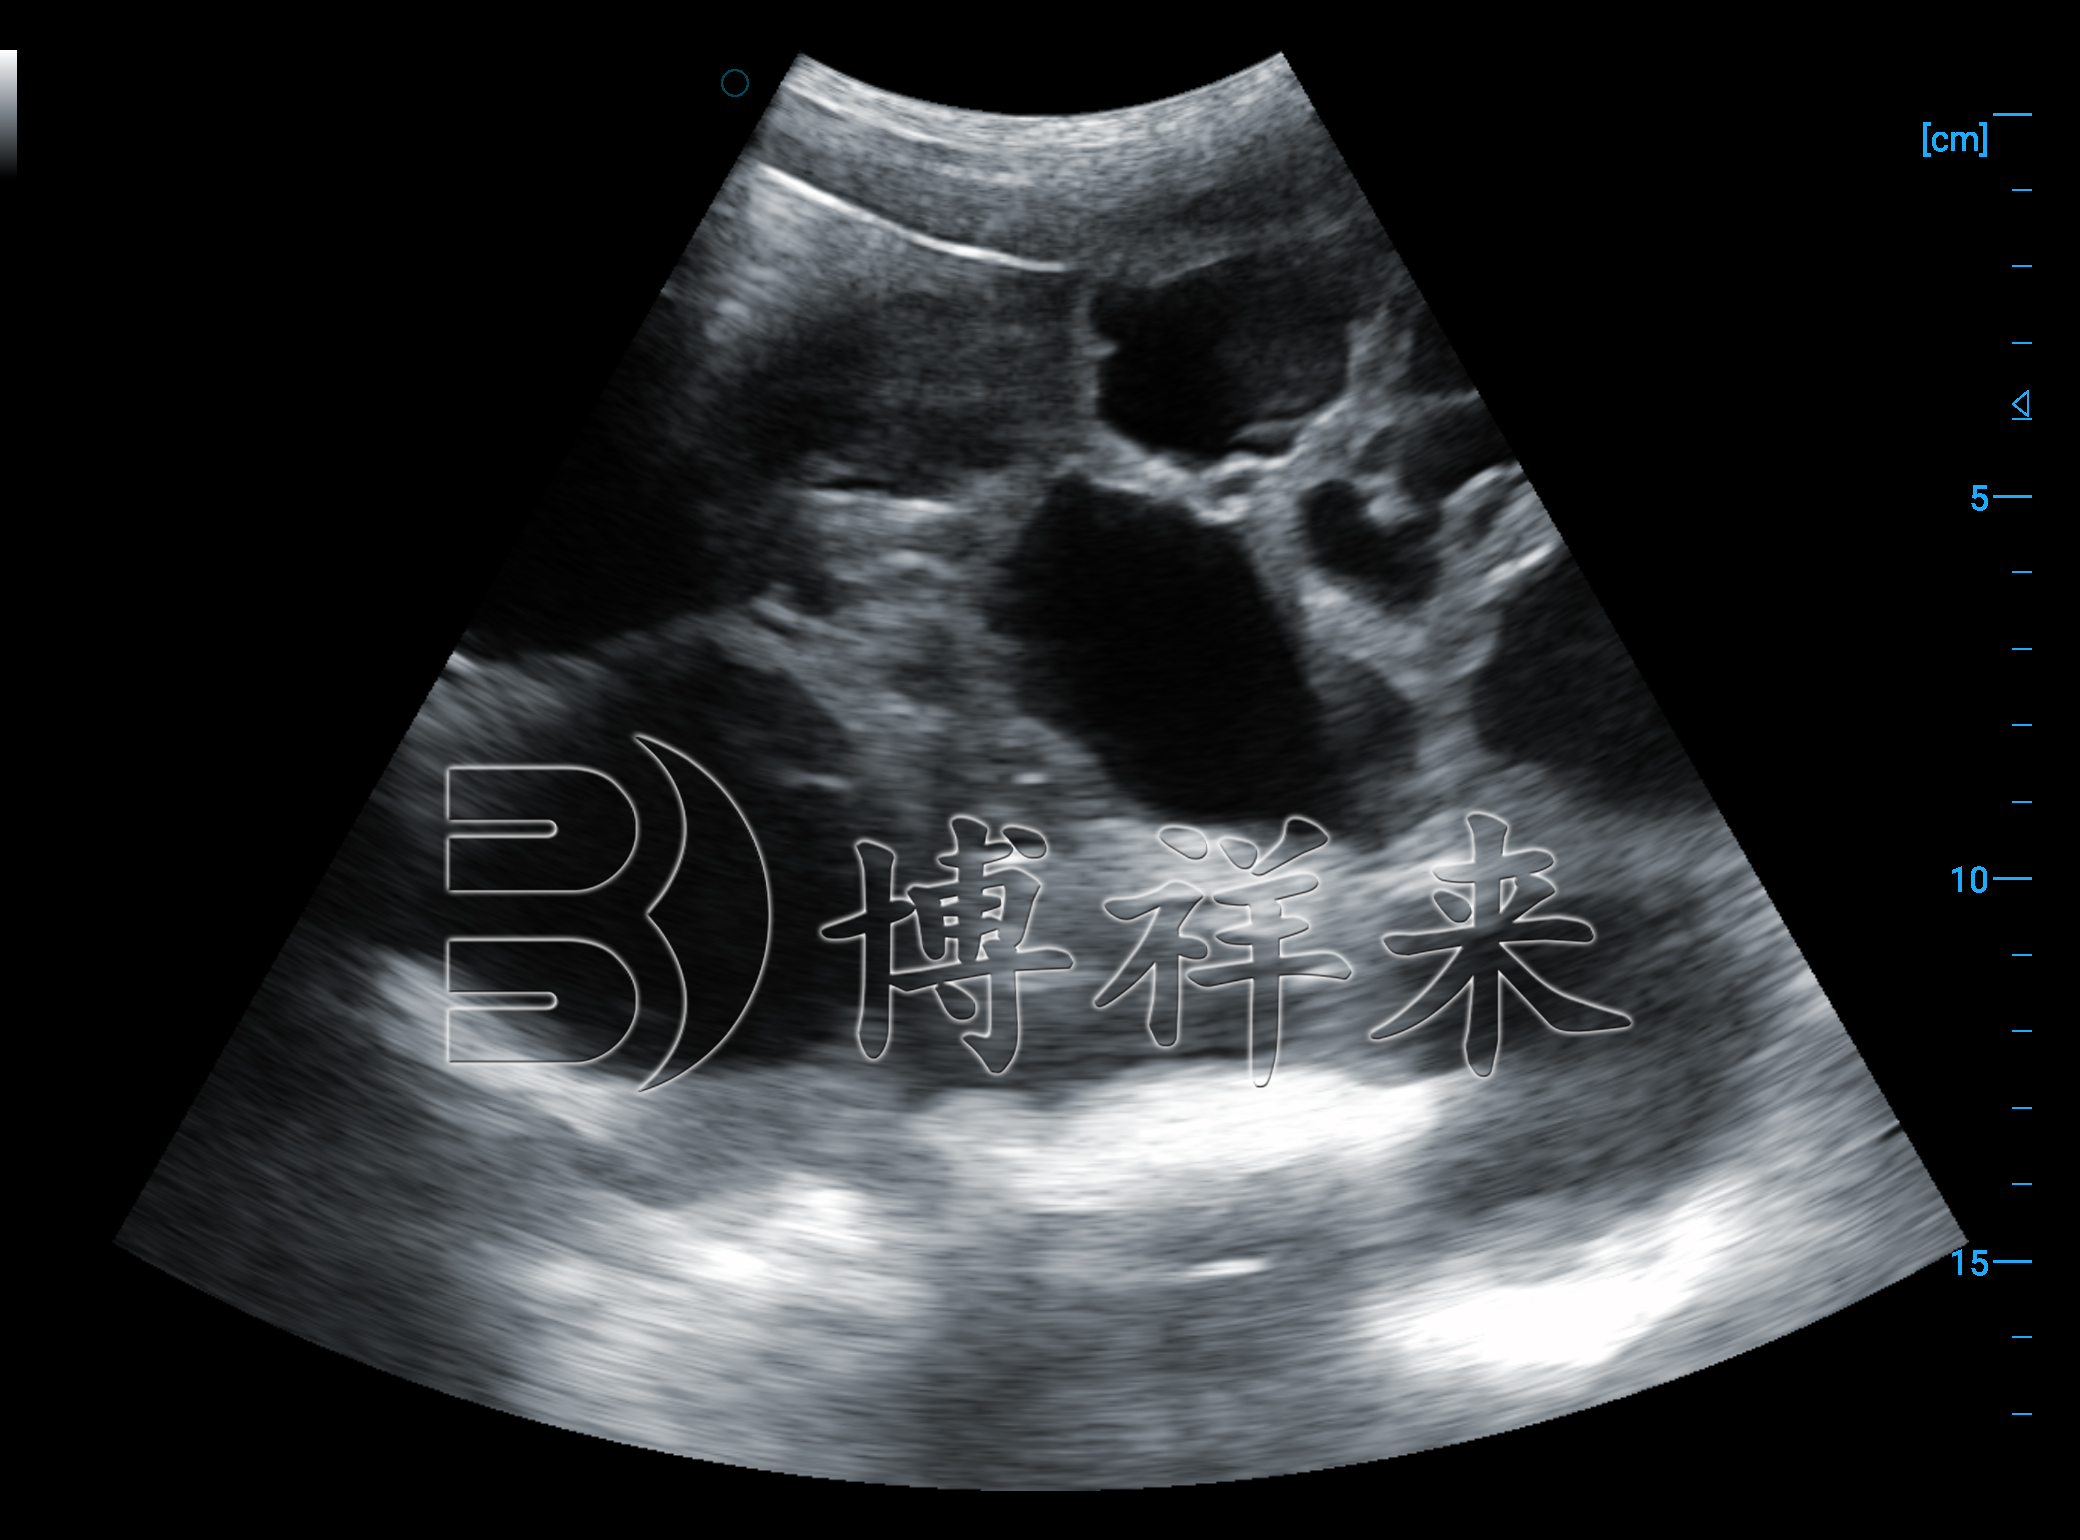

在配种后 20 天左右,母猪子宫内的孕囊开始形成明显的无回声结构。在猪用B超机显示的影像中,孕囊呈黑色圆形或椭圆形暗区,周围由亮度较高的子宫壁包围。随着妊娠天数的增加,孕囊会不断长大,并逐渐出现胎体、胎盘等结构。

妊娠 24–35 天 是看到孕囊***清晰的阶段,此时孕囊大小接近一致,不易重叠,是估算胎仔数的黄金窗口。

在多胎母猪的图像中,常可看到多个黑色孕囊排列在同一子宫角内,技术员通过对不同角度的扫描,就能推算出胎仔数量。